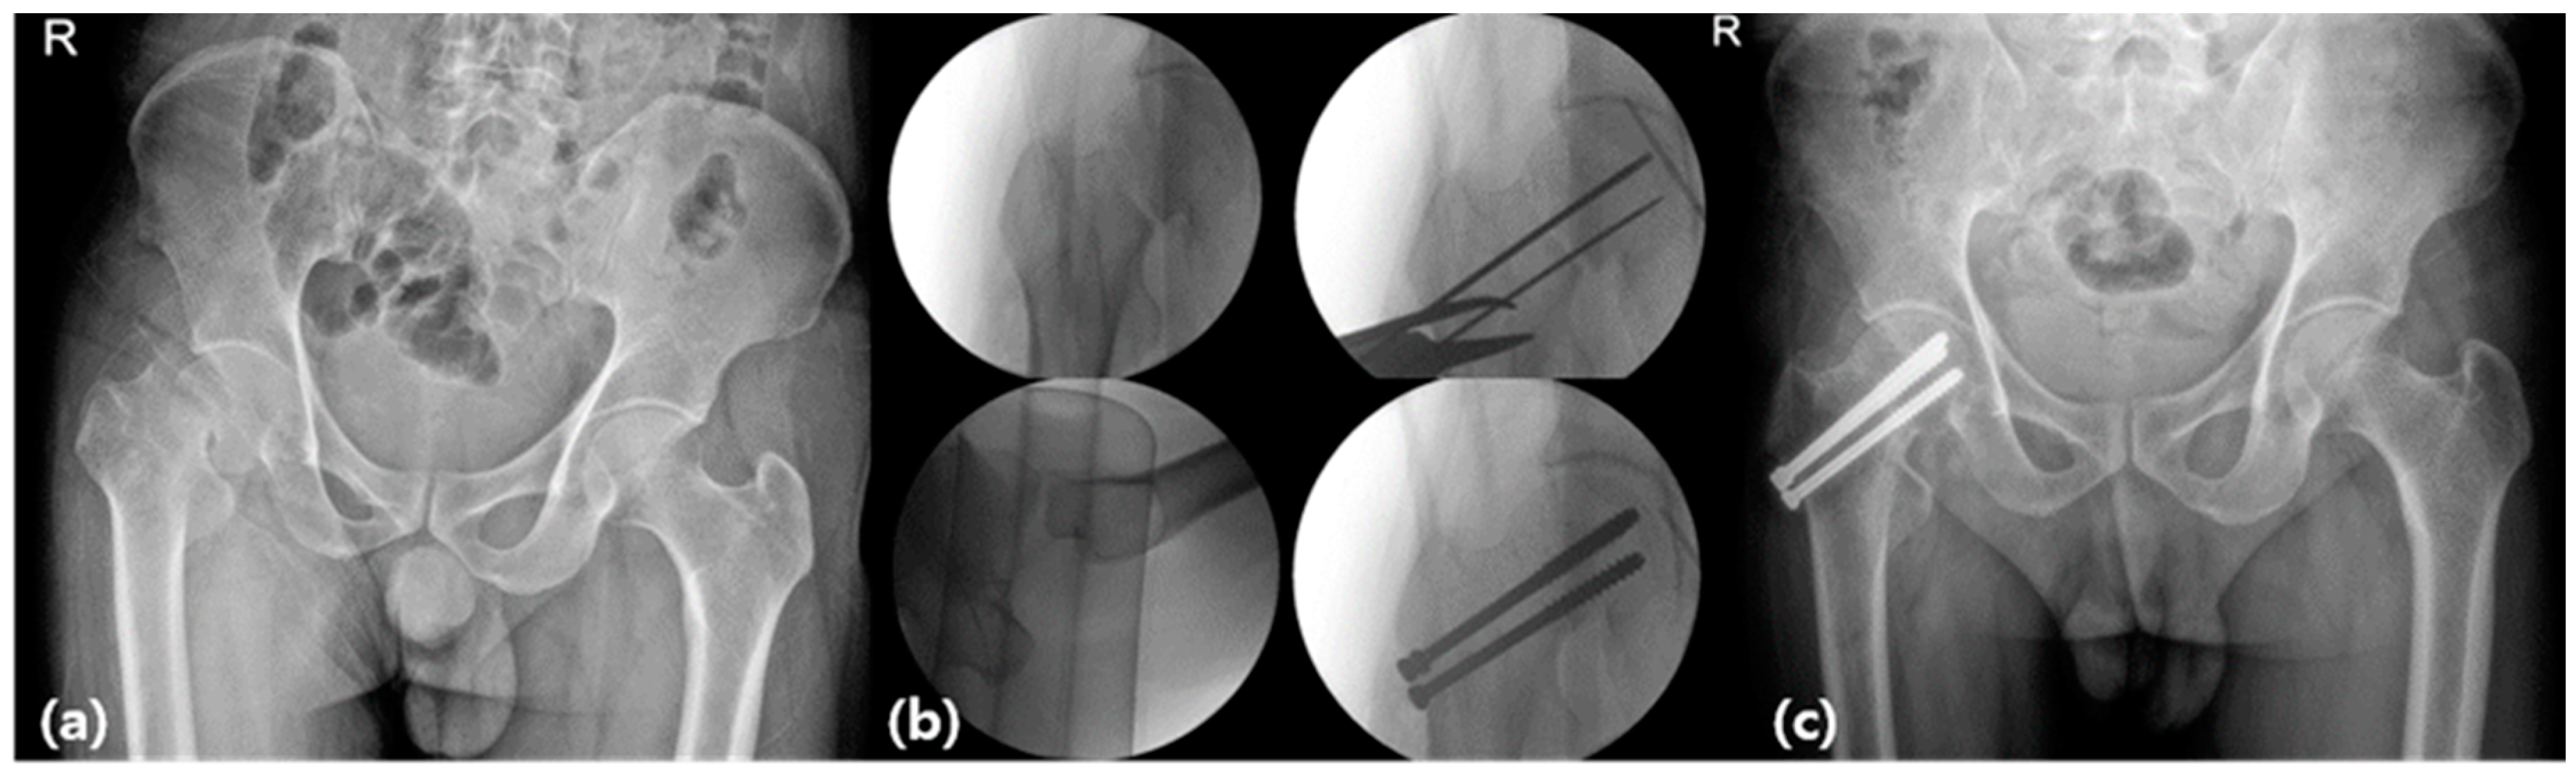

2.4. Procedure